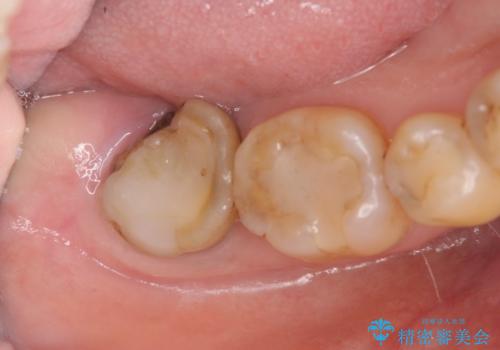

歯周病に対する全体治療

- 近医で「重度の歯周病です、入れ歯にする必要がある。」、と言われ入れ歯以外の方法がないか相談にみえられました。

再生治療、歯周外科を行うことで歯周病治療を行い、残すことのできる歯の歯周環境を整える。

残すことのできない歯は抜去したのち骨造成を含めたインプラント治療を行い、しっかりとした咬合関係を確立していきます。

治療期間はかかりましたが、しっかりと歯周病治療・インプラント治療を行ったおかげで歯周病の状態は非常に良くなり、安定した咬合関係を確立することができました。